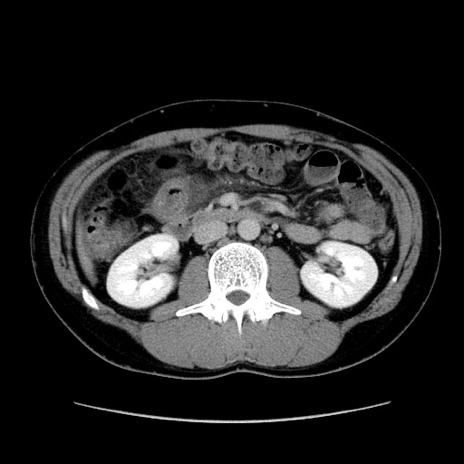

症例36(横断像)

【症例】20歳代 男性

【主訴】心窩部痛

【現病歴】今朝より上腹部痛あり。一旦軽快していたが再度出現したため救急要請。昨日夕に白身の魚を含む刺身を食べた。

【身体所見】BP 136/89mmHg、HR 74/min、BT 37.0℃、腹部:膨満、軟、心窩部に圧痛あり。反跳痛なし、筋性防御なし、腸雑音やや亢進あり。

【データ】WBC 17700、CRP 0.48